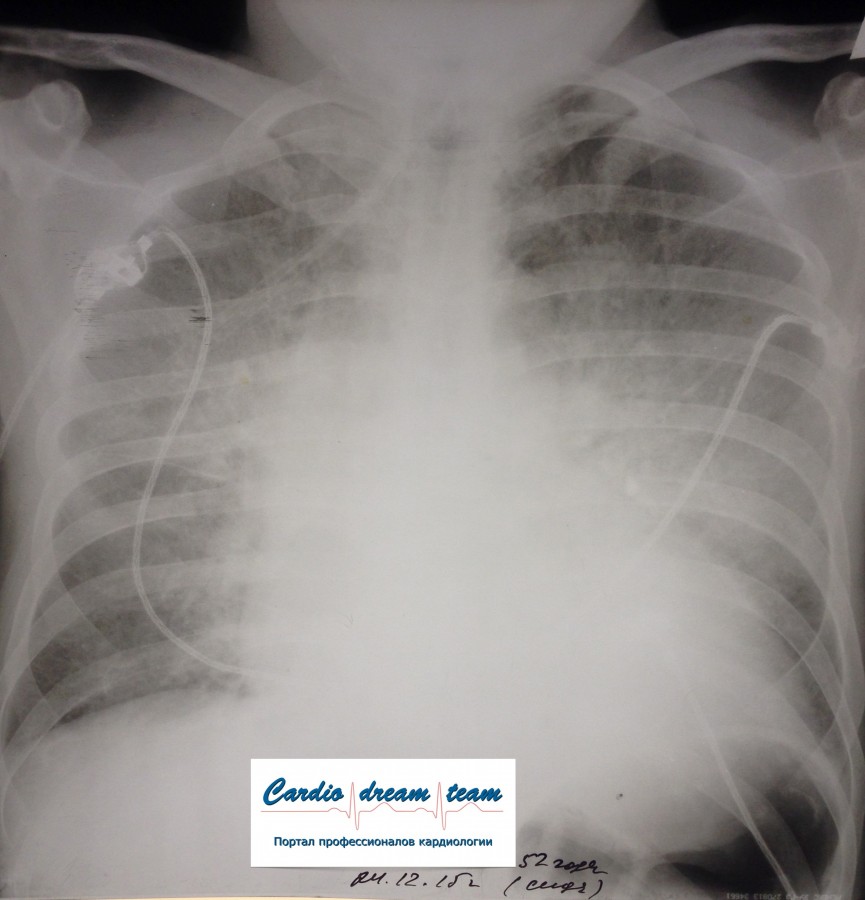

Не обсуждалась Дата 23-ИЮЛ-15 ОПИСАНИЕ: Проведена рентгенография органов грудной клетки в прямой проекции, положение лежа, условия ПИТ Легочные поля: неравномерно прозрачны за счет сосудистого обогащения, в базальных отделах с обеих сторон, отмечается сгущение легочного рисунка, за счет гиповентиляции, в плевральных полостях жидкость Легочный рисунок: Изменен по смешанному типу: обогащен за счет сосудистого компонента, деформирован за счет склероза. Корни: бесструктурны, расширены за счет сосудистого компонента, обогащены Синусы: определяется наличие жидкости по линии 5 ребра Сердце: широко лежит на диафрагме отмечается расширение границ сердечной тени влево, вправо экг-электроды. ЗАКЛЮЧЕНИЕ: Рентген-признаки 2-х стороннего гидроторакса с гиповентиляцией базальных сегментов.. Признаки застоя по МКК 2 степени (умеренно выраженный). Пневмосклероз. Р-признаки гипертрофии левого желудочка сердца. Склероз аорты.